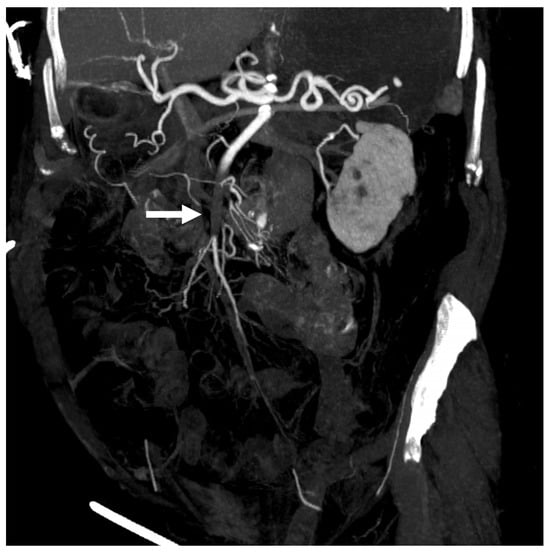

2. Case Report